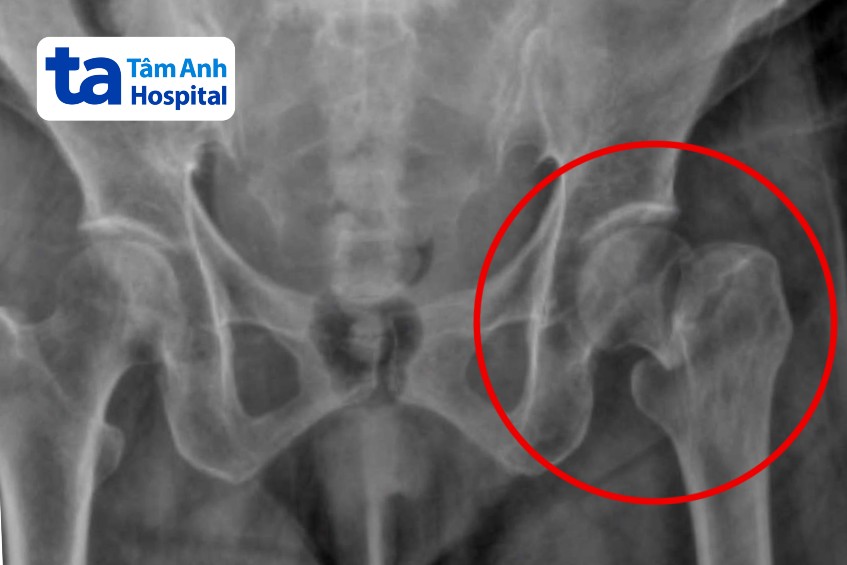

Bà Hòa, 75 tuổi, đau dữ dội vùng háng sau trượt té tại nhà, gãy cổ xương đùi hoàn toàn, phải thay khớp nhân tạo khẩn cấp.

Bà Hòa được đưa đến Bệnh viện Đa khoa Tâm Anh TP HCM trong tình trạng chân trái đổ ra ngoài và gần như bất động. Trước đó, sau khi bị trượt té, bà cố gắng tự đứng dậy nên tiếp tục ngã thêm hai lần nữa.

ThS.BS Hồ Đức Lộc, Trung tâm Chấn thương Chỉnh hình, cho biết các cú ngã liên tiếp khiến xương đùi và háng của bà Hòa bị tác động mạnh, gãy hoàn toàn. Nhận định đây là trường hợp cần được can thiệp phẫu thuật càng sớm càng tốt, bác sĩ Lộc đã khởi động chương trình Mổ cấp cứu gãy xương trong 24-48 giờ. Chương trình này đảm bảo từ thời điểm nhập viện đến khi kết thúc phẫu thuật không quá 48 giờ.